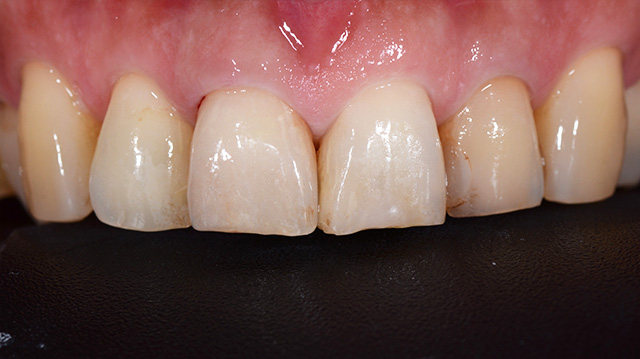

| 年代・性別 | 40代 男性 |

|---|---|

| 主訴 | 前歯の被せ物が取れた |

| 治療回数 | 3回 |

| 治療期間 | 約1ヶ月 |

| 費用 | 仮歯 5,500円 ジルコニアクラウン 176,000円 |